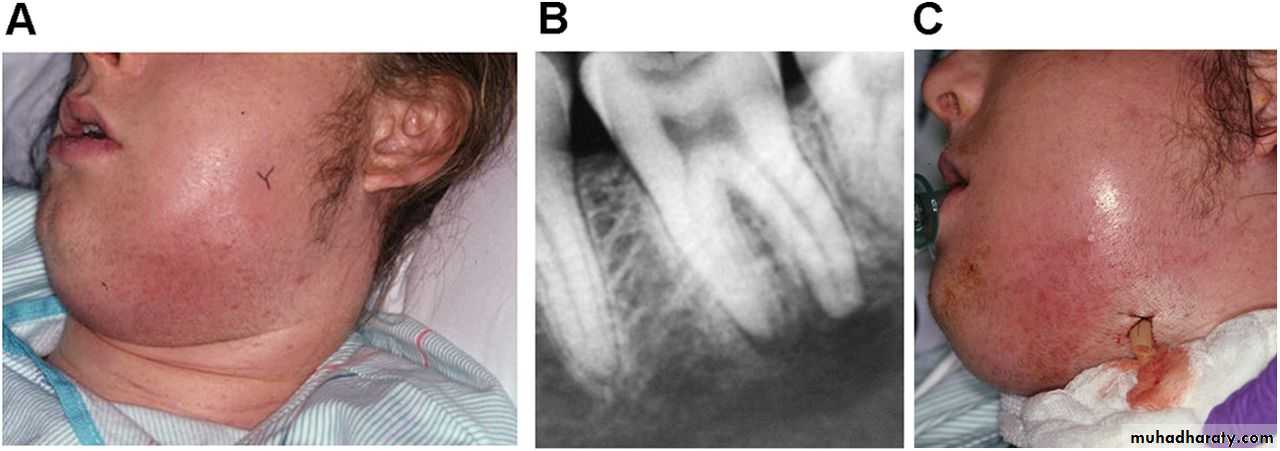

Acute Apical Abscess

Acute apical abscess (AAA) is a localized or diffuse liquefaction lesion of pulpal origin that destroys periradicular tissues and a severe inflammatory response to microbial and nonbacterial irritants from a necrotic pulp.The development of an abscess in apical periodontitis lesions is probably caused by invasion of a combination of specific pyogenic bacteria in the inflamed periapical tissues.